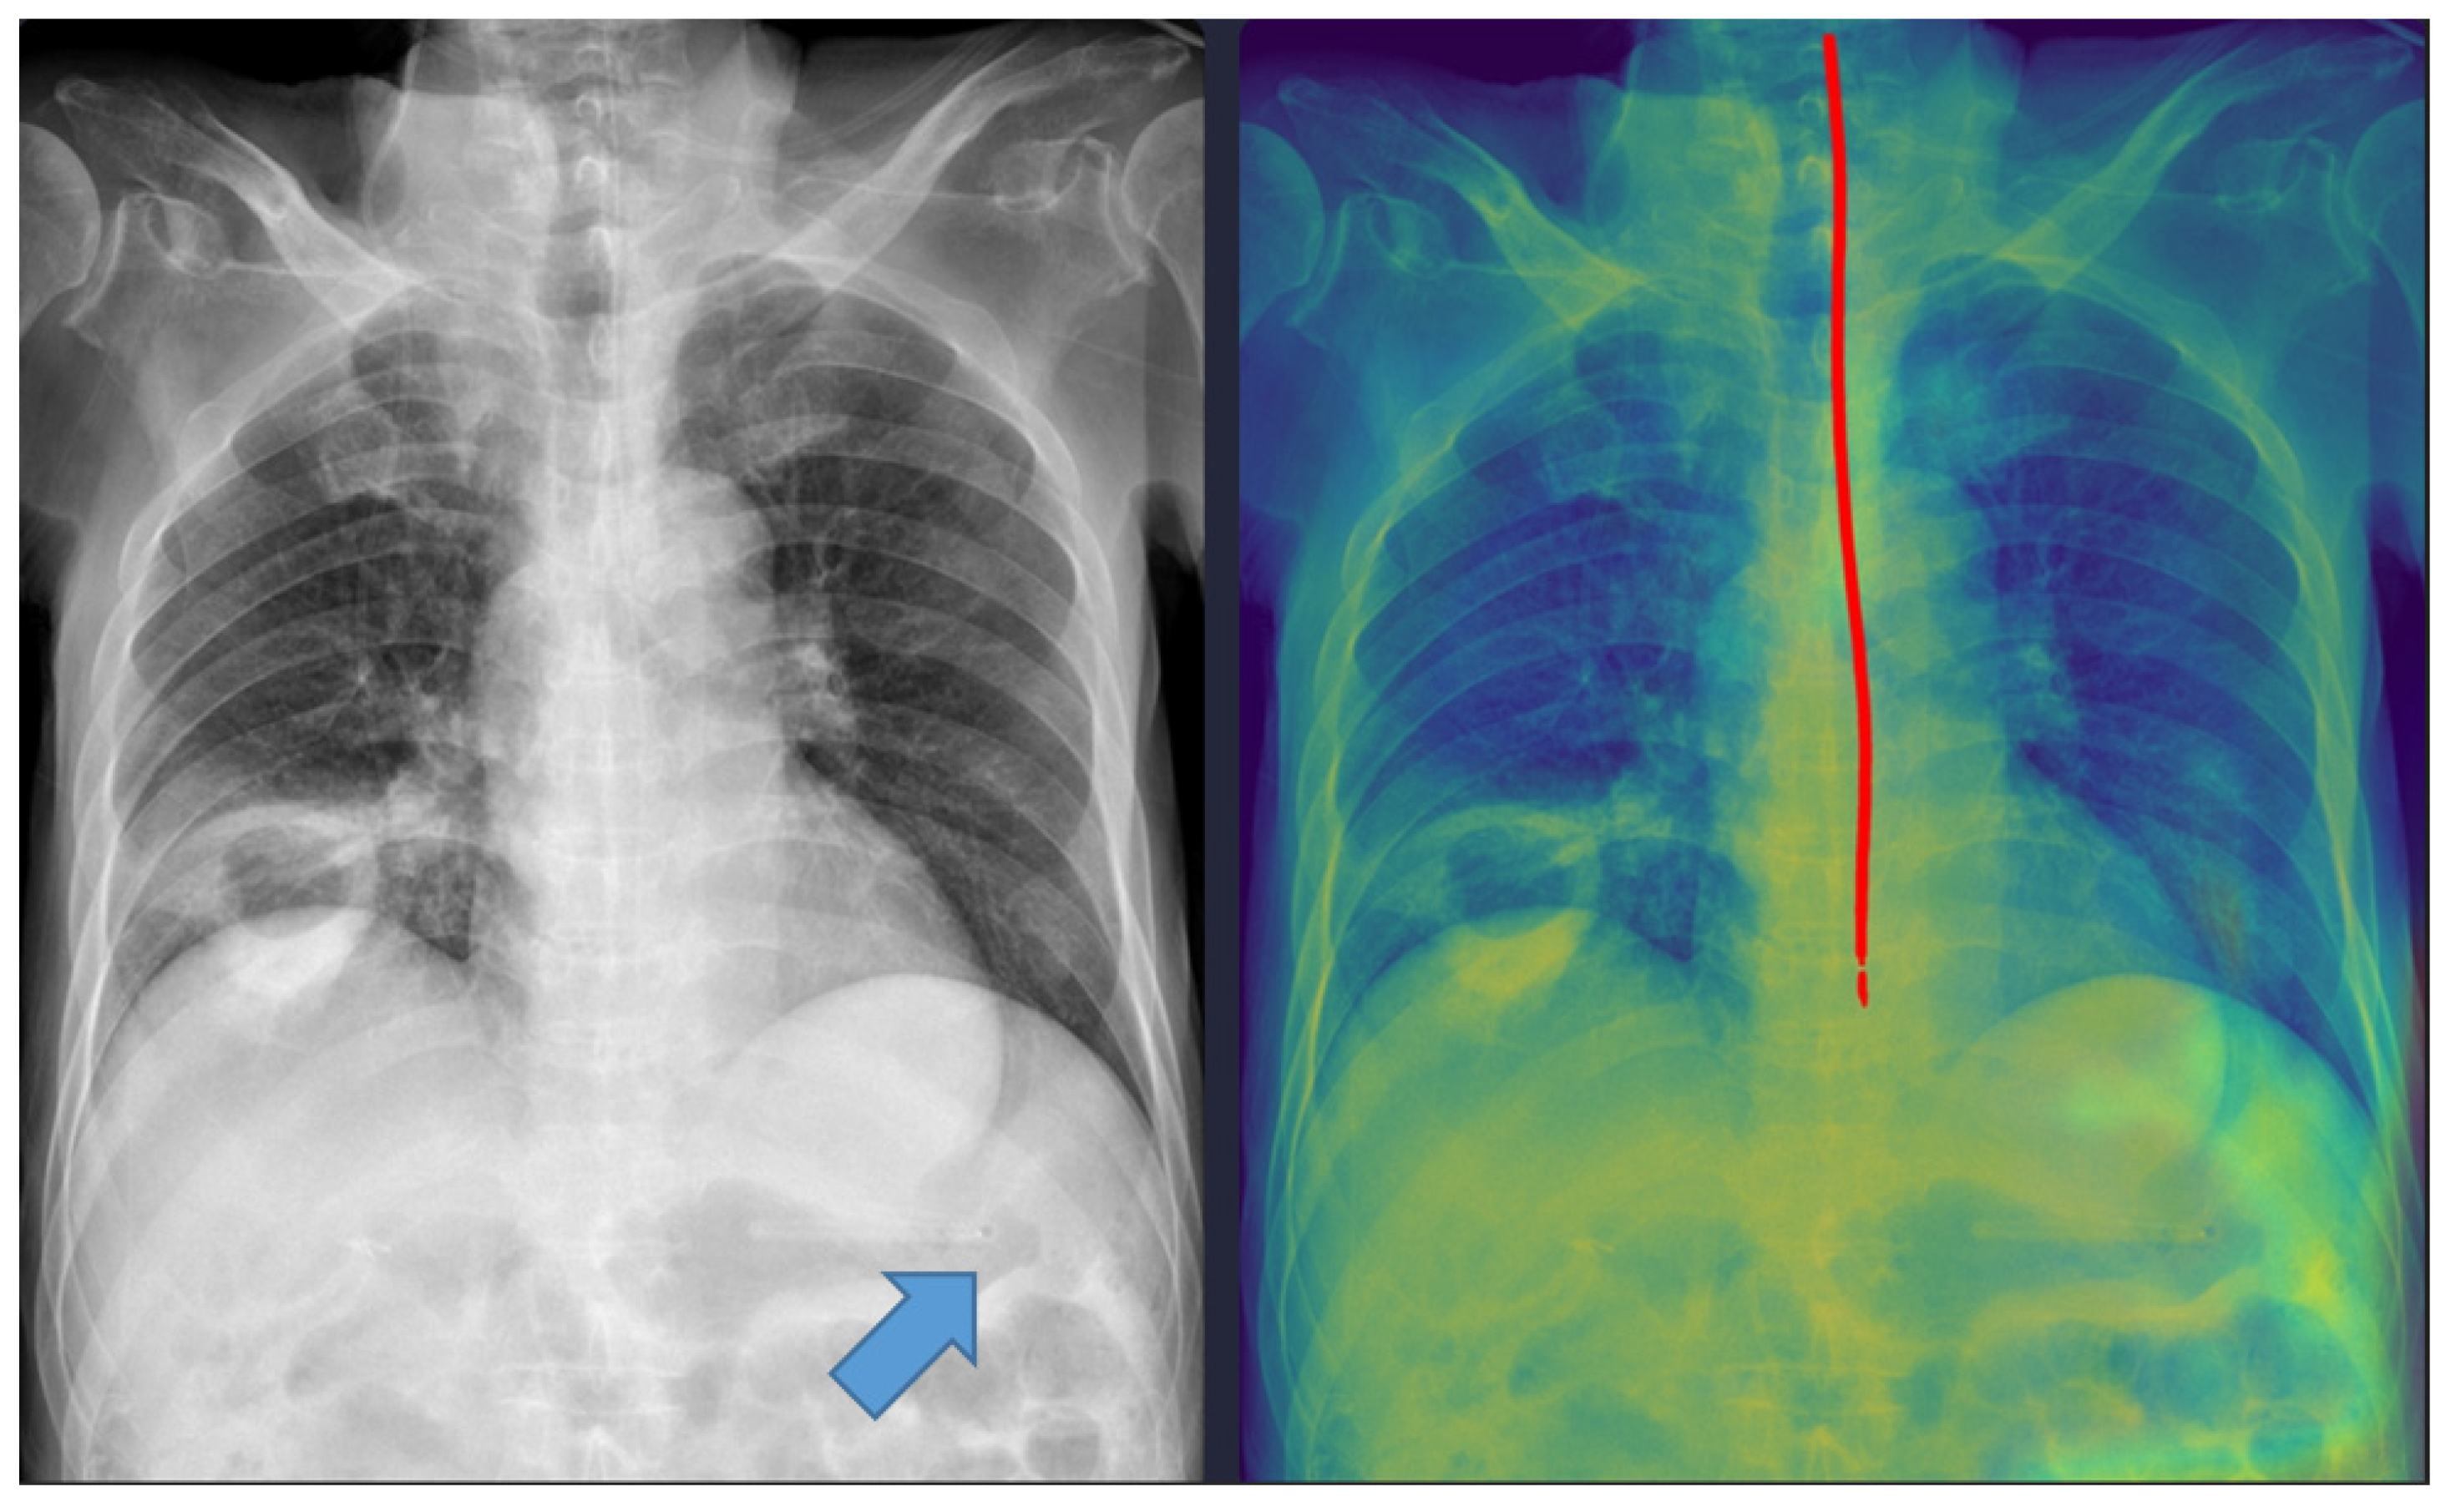

Representative examples of misclassified cases are shown in Figure 2 and Figure 3. The most critical failure involved an NG tube coiled at the indicated site in Figure 2, which suggested incomplete placement and a significant safety risk. The DL model misclassified this case as ‘complete’ based solely on the position of the tip projected below the gastroesophageal junction. Technically, this false-positive classification was highly likely due to the scarcity of such complex, coiled morphological features in the training dataset. While the segmentation module correctly identified the general tube structure, the dual-stage model failed to recognize this pronounced looping or coiling as an immediate risk factor, resulting in the classification module overriding the critical incomplete placement status. This finding identifies a crucial, previously unanticipated failure mode in the model’s design and carries substantial clinical significance, as initiating feeding through a coiled tube presents a high risk of aspiration pneumonia. Moving forward, efforts must focus on incorporating a greater diversity of these rare, yet clinically critical, coiled cases into the dataset to enhance the robustness of the tube segmentation process, thereby ensuring improved and safer clinical implementation. In Figure 3, the DL model failed to draw the entire trajectory of the NG tube and misclassified a complete case as incomplete. A representative example of a correctly classified case is shown in Figure 4. The tip of the NG tube is placed under the gastroesophageal junction and is safe to feed. Because most cases were correctly positioned (=95%), prevalence bias likely inflated the AC1 coefficient, and κ was lower despite near-identical classifications. Future studies should include more incomplete cases to obtain stable reliability estimates [12]. Prevalence-adjusted bias-adjusted kappa (PABAK) estimates were also evaluated with bootstrapping confidence intervals [13]. The results of the agreement among physicians and the DL model are shown in Table 4. Cohen’s κ showed the smallest estimate of 0.644 (95% confidence interval (CI): 0.366–0.922), which increased when using PABAK (0.911 (95% CI: 0.812–0.967)) and Gwet’s AC1 coefficient (0.956 (95% CI: 0.907–0.991)).

Five cases were misclassified as incomplete, although the NG tube was correctly positioned in the stomach (Figure 3). In these cases, the model’s predicted pathway stopped midway, likely because radiopaque structures such as the spine overlapped with the tube. This finding indicates that the model requires additional training with a more diverse dataset to improve its robustness against anatomical noise.

Figure 3. A misclassified complete nasogastric tube case identified as incomplete by the model. The arrow indicates the tip of the nasogastric tube. The red line represents the trajectory of the nasogastric tube as identified by the deep learning model.